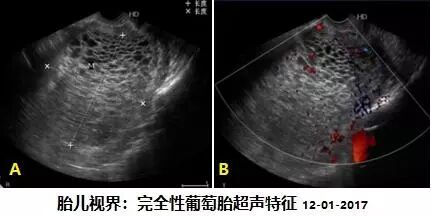

完全性葡萄胎:超声表现为子宫增大,常大于孕周,宫腔内无妊娠囊及胚胎结构,而充满低回声含液体的葡萄胎囊泡,蜂窝状无回声小囊呈葡萄样改变,彩色多普勒示宫腔内蜂窝状液性暗区内几乎无血流信号。(见图

四、完全性葡萄胎的子宫声像及彩超表现(经阴道超声)。左:灰阶(即黑白超声),无孕囊、无胚胎。右:彩色多普勒血流显像检测葡萄胎内无血流信号检出。